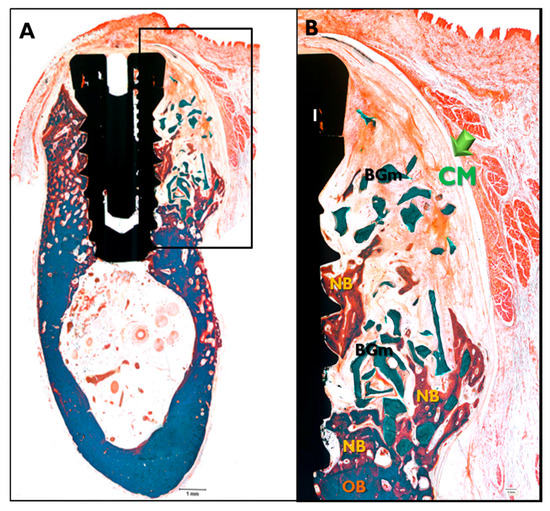

2.3.3. Histologic Findings

In the CM transplanted animals (Figure 8), a new bone formation was observed and fibrous connective tissues and graft materials were also observed in buccal peri-implant dehiscence defect areas. In some specimens, small amounts of membranes were observed. In the EI-BCM and CM transplanted animals (Figure 9), new bone, fibrous connective tissue, and graft materials were observed in the peri-implant dehiscence defect area. The EI-BC membranes remained at eight weeks in a similar pattern to the CM group, but expansion of the membrane was observed in some specimens.

Figure 8.

Histological sections specimen in CM transplanted animals. NB, new bone; BGm, bone graft material; OB, old bone; I, implant (Goldner Trichrome stained; original magnifications: 12.5× (A); and 40× (B)).

Figure 9.

Histological sections specimen in EI-BCM transplanted animal. NB, new bone; BGm, bone graft material; OB, old bone; I, implant (Goldner Trichrome stained; original magnifications: 12.5× (A); and 40× (B)).